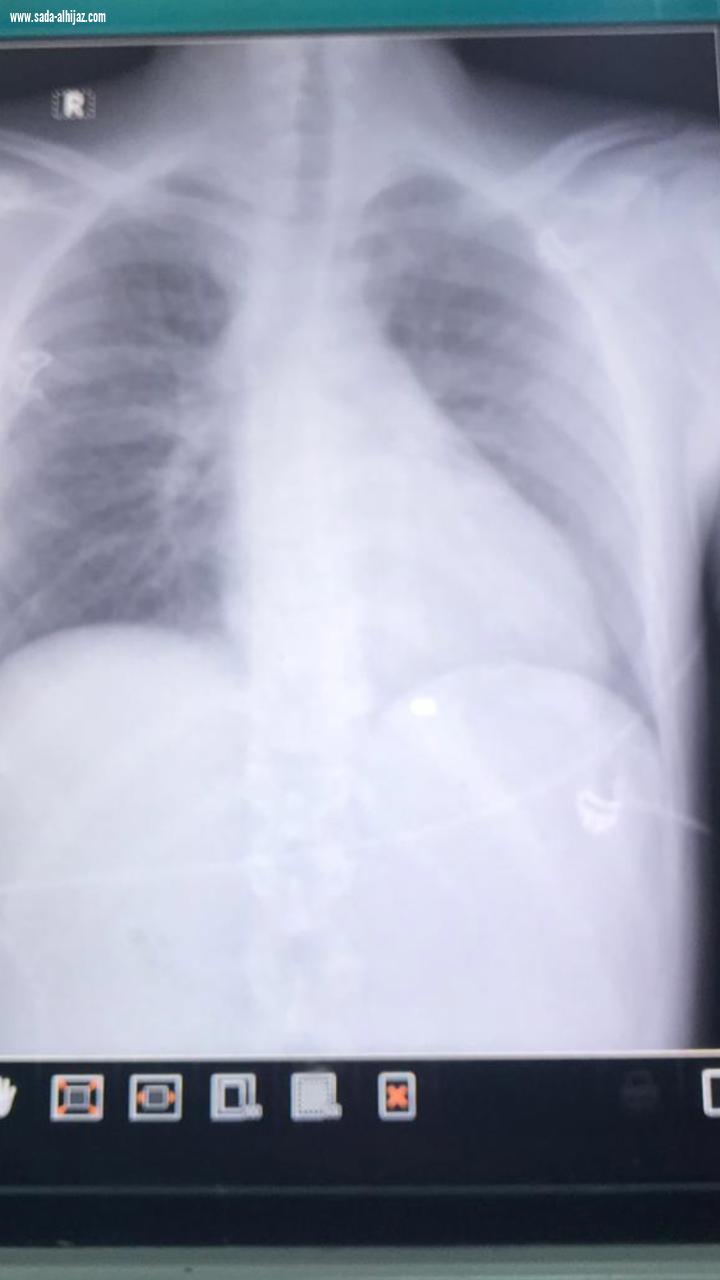

أجرى مستشفى الملك فهد العام بجدة عملية قلب مفتوح عاجلة بالغة الخطورة لمواطن مصاب بطلق ناري في البطين الأيمن للقلب ، حيث نجح بفضل الله الطاقم الطبي من جراحي القلب و الصدر بالمستشفى من إجراء عملية استخراج رصاصة أستقرت في البطين الأيمن للمواطن ، في ساعة متأخرة من يوم الخميس الماضي .

و في التفاصيل أستقبل قسم الطوارئ بالمستشفى مواطن يبلغ من العمر 17 عاماً حضر بواسطة سيارة اسعاف تابعة لإحدى المستشفيات الخاصة ، تعرض لطلق ناري في البطين الأيمن للقلب مع وجود نزيف شديد ، و تم التعامل مع الحالة على الفور لدى وصول المصاب لقسم الطوراىء ، و نقله مباشرة إلى غرفة العمليات ، و إجراء عملية قلب مفتوح بشكل عاجل و إستخراج الرصاصة و سحب التجمع الدموي في غشاء التامور المحيط بالقلب و ترقيع جدار البطين الأيمن ، و تم وقف النزيف من الصدر بمشاركة الدكتور فواز ألطف و الدكتور محمد شفيق جراحين القلب و الصدر وتم إنقاذ المريض بفضل من الله ، و لا زال المصاب بالعناية المركزة في حالة مستقرة خاضعاً للعناية و المتابعة الطبية اللازمة .